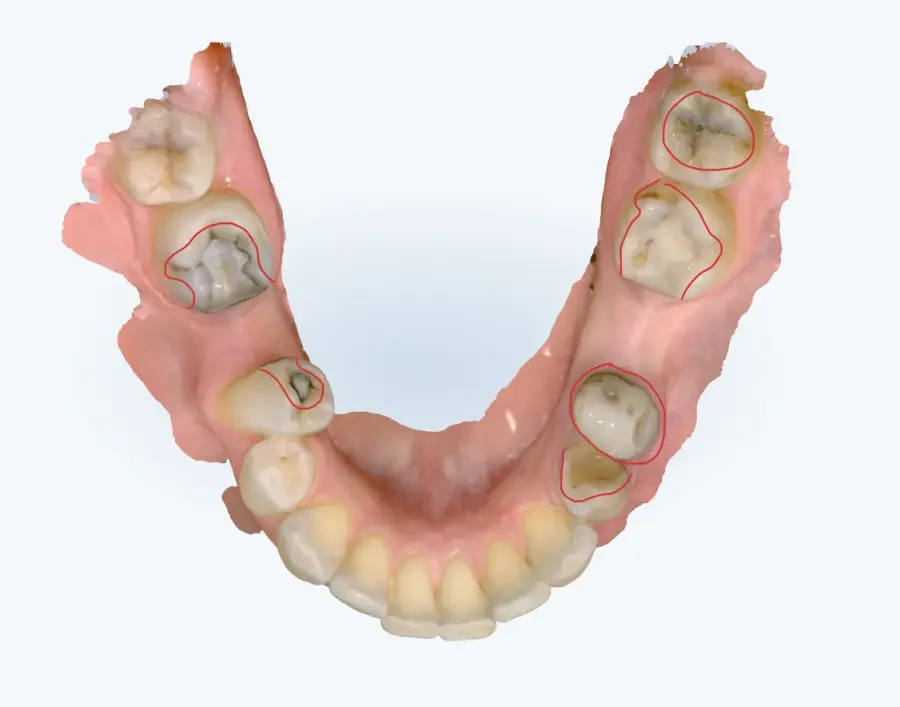

Papildus norādām, ka arī no intraorālās skenēšanas datiem (tostarp ekrānšāviņiem) ir identificējamas vairākas klīniski nozīmīgas problēmas, tai skaitā:

* aktīvi kariozi bojājumi,

* bojātas, lūzušas un plaisājušas plombes,

* vairāku zobu audu apjoma zudums,

* citas strukturālas izmaiņas, kas var ietekmēt turpmāko ortodontisko ārstēšanu.